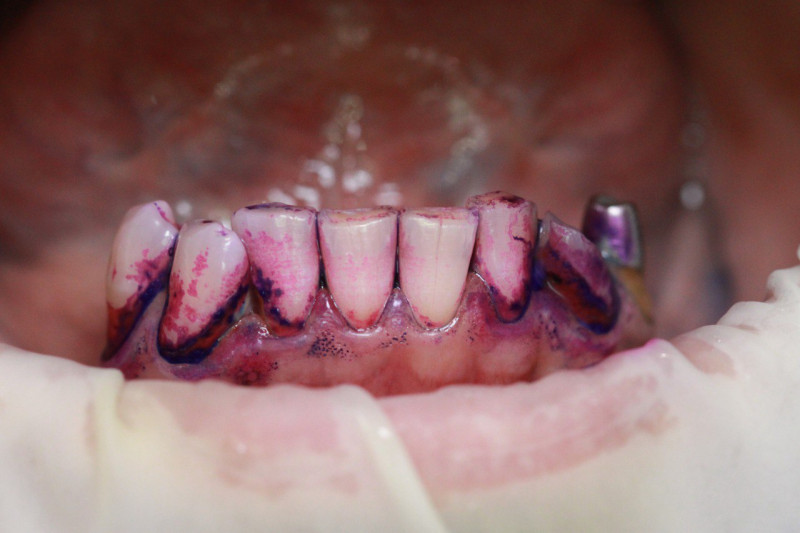

Index Dual работает по принципу селективного окрашивания: свежий налёт (до 24 часов) становится розовым, а зрелый кариесогенный налёт (более 24 часов) — синим.

Двухтоновая формула Дифференцирует свежую и старую биопленку

• Чёткая контрастность: Синий цвет настолько интенсивный, что его невозможно спутать с естественной пигментацией или гиперемией дёсен.

• Скорость реакции: Окрашивание происходит мгновенно после контакта с биоплёнкой.

Используйте микробраш или ватную палочку. Нанесите на все поверхности зубов, подождите 10–20 секунд и попросите пациента прополоскать рот водой.